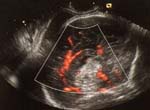

- Le Doppler couleur montre l’artère péri-calleuse incluse dans le lipome.

- Existence d’une artère affluente au doppler couleur.